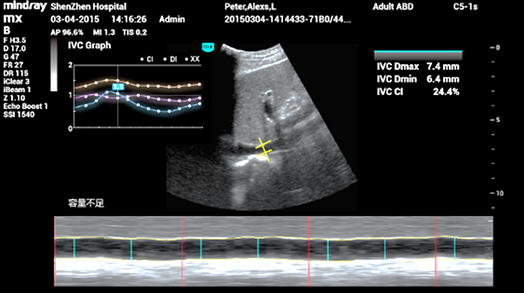

3Smart IVC

Automatische meting van IVC-parameters (Inferior Vena Cava) helpt bij de beoordeling van de volumestatus en begeleidt de vloeistoftherapie. Een grafiek van de parameterwijziging voor CI of DI en IVCV om veranderingen van ernstig zieke pati?nten te monitoren.